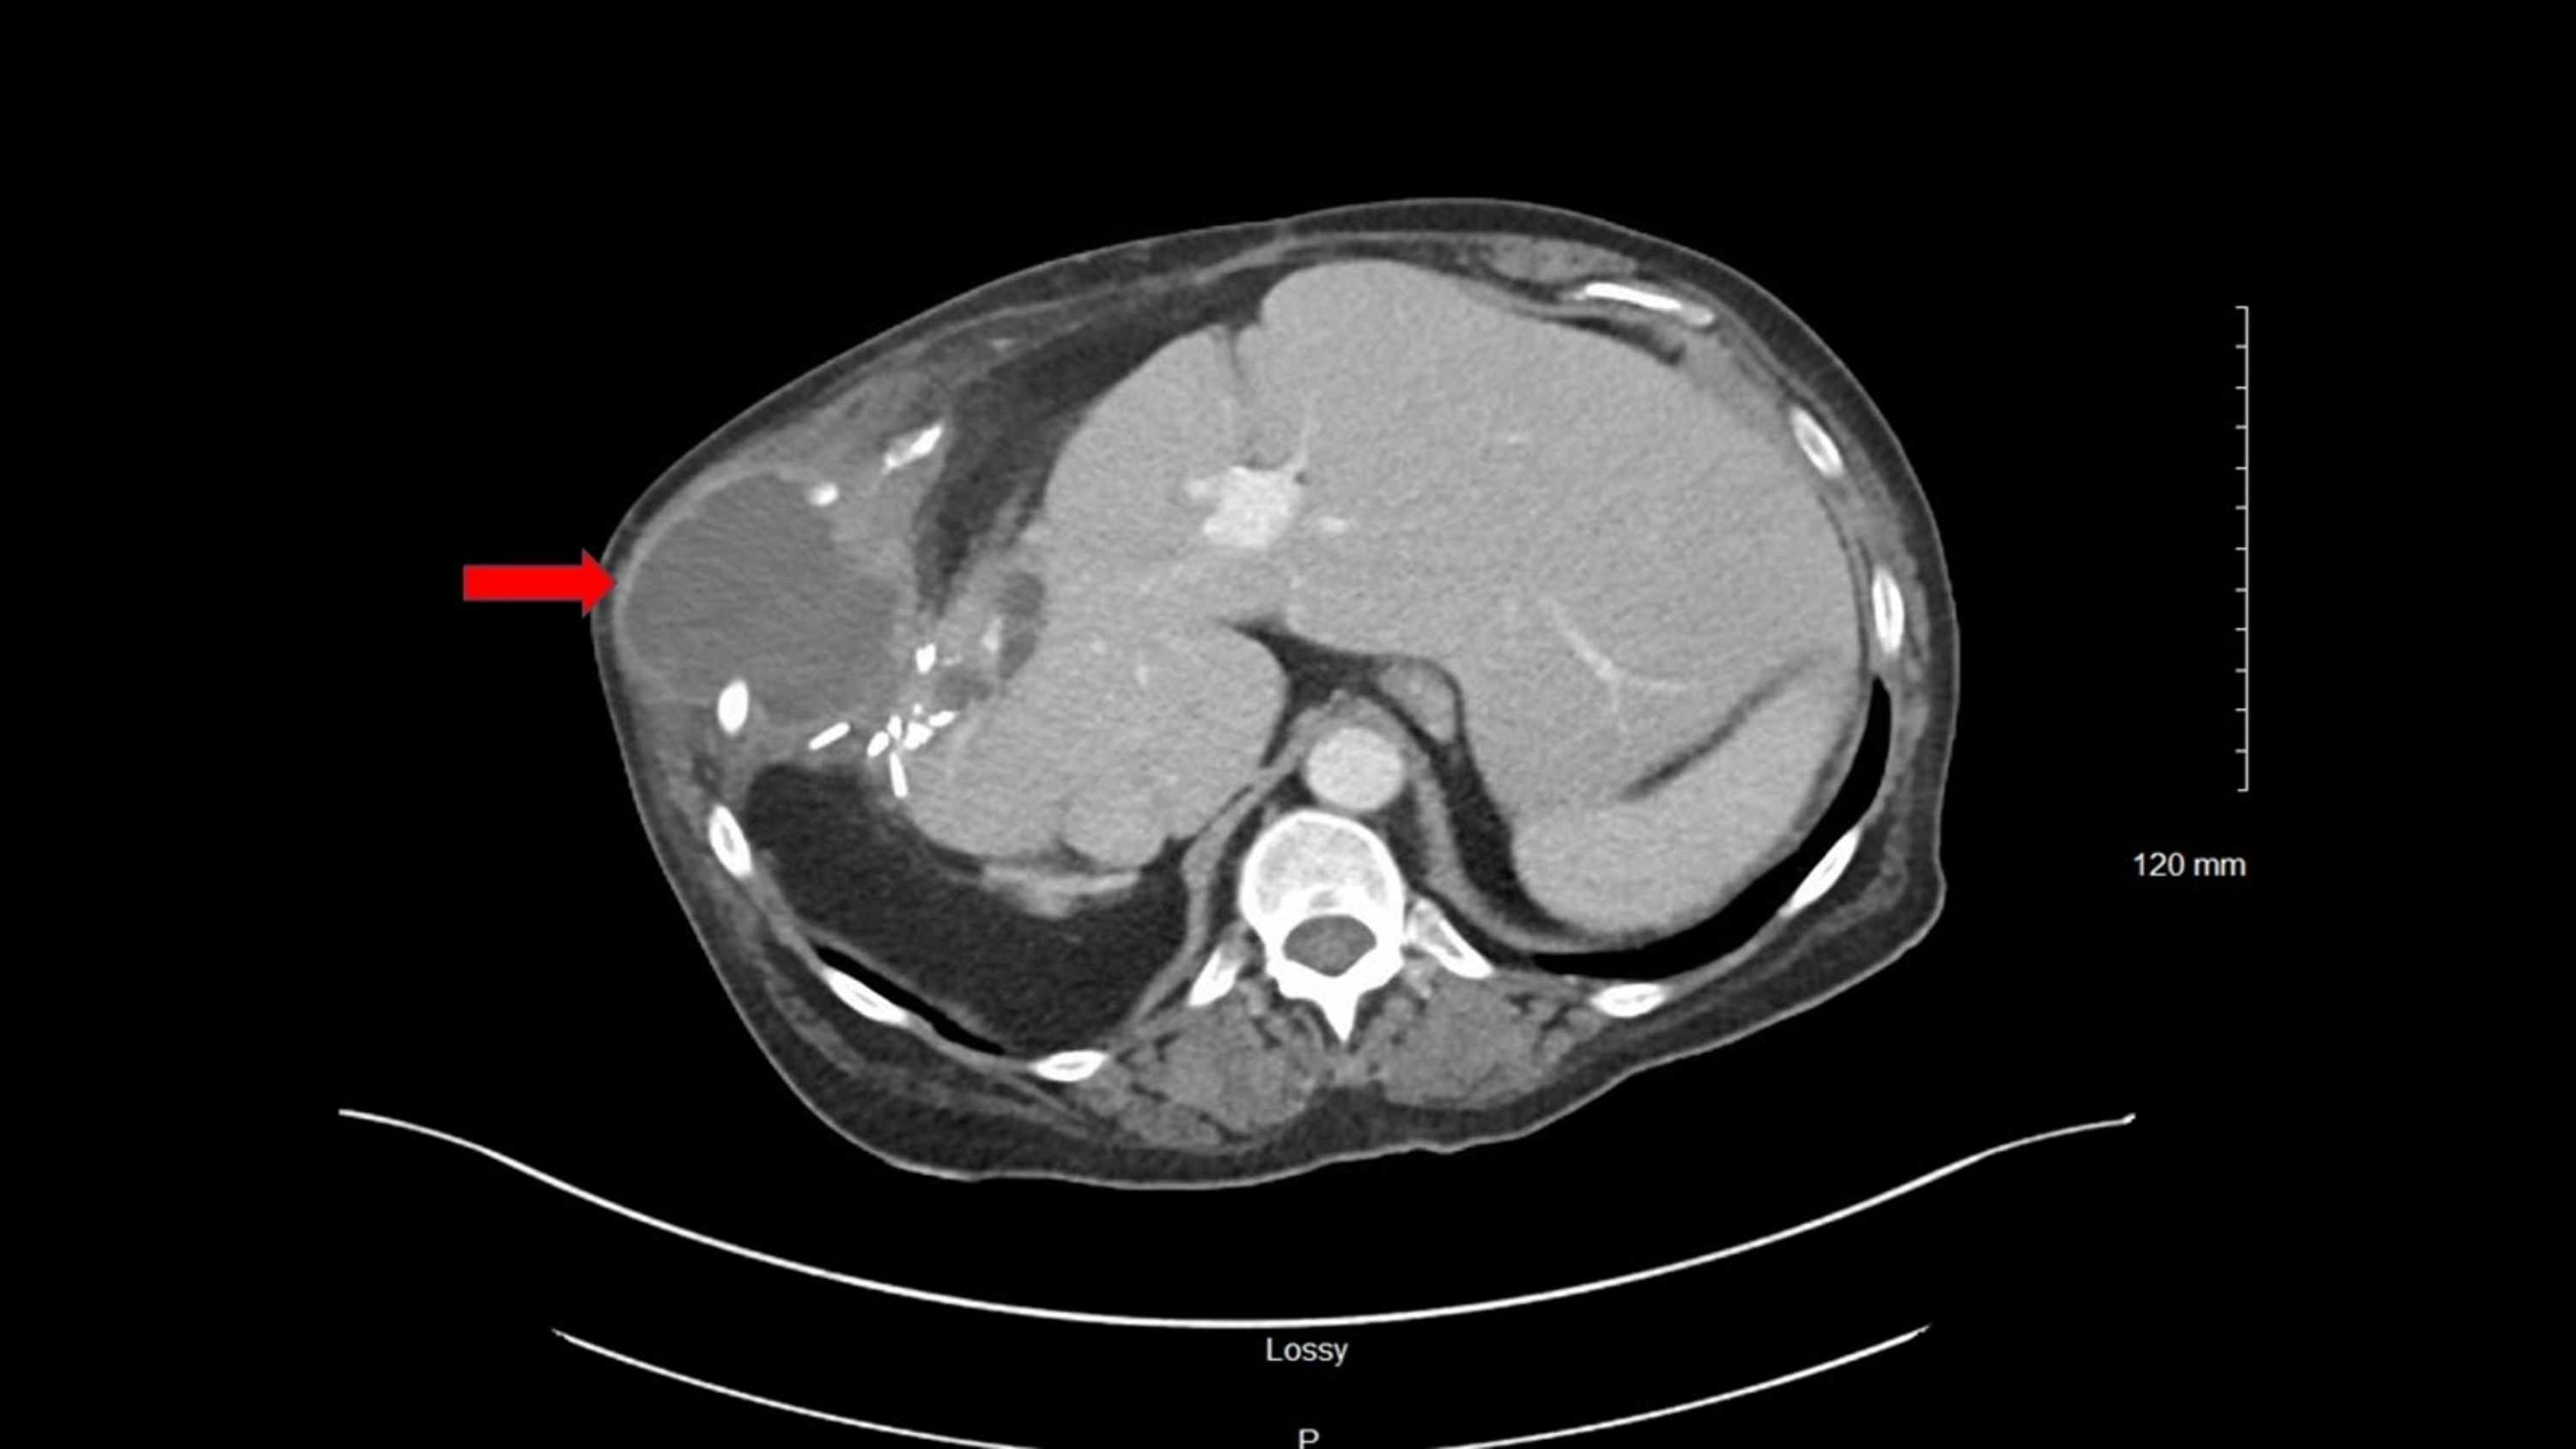

Cureus A Rare Case of Crohn’s Disease Manifesting as a Large Liver Abscess Crohn's Disease In patients with crohn’s disease, abscesses, or collections of pus, often develop in the abdomen, pelvis, or around the. Percutaneous abscess drainage (pad) is the preferred treatment for treating abscesses with crohn’s disease. Crohn's disease is an inflammatory bowel disease that causes chronic inflammation of the gi tract,. Abdominal and pelvic abscesses in crohn’s disease occur spontaneously or as a.. Abscess Crohn's Disease.

Radiology case Abscess, Crohn's disease Abscess Crohn's Disease Abdominal and pelvic abscesses in crohn’s disease occur spontaneously or as a. Crohn's disease is characterized by inflammation that involves the full thickness of the bowel wall, which can lead. Crohn's disease (cd) is a chronic inflammatory disease evolving by acute episodes separated by periods of. Crohn's disease is an inflammatory bowel disease that causes chronic inflammation of the gi. Abscess Crohn's Disease.

Abscess formation in Crohn disease. Axial (a) and coronal... Download Abscess Crohn's Disease Crohn's disease is characterized by inflammation that involves the full thickness of the bowel wall, which can lead. For this reason, perforating complications such as intra. The chronic intestinal inflammation that occurs in crohn's disease can lead to the development over time of intestinal complications such as strictures, fistulas, and abscesses. During pad, your doctor will make a small cut. Abscess Crohn's Disease.

Figure 3 from Review of IntraAbdominal Abscess in Crohn's Disease Abscess Crohn's Disease Abdominal and pelvic abscesses in crohn’s disease occur spontaneously or as a. Crohn's disease, in most cases, is a chronic, progressive, destructive disease (summary statement). The chronic intestinal inflammation that occurs in crohn's disease can lead to the development over time of intestinal complications such as strictures, fistulas, and abscesses. Percutaneous abscess drainage (pad) is the preferred treatment for treating. Abscess Crohn's Disease.

Crohn disease. CT scan obtained with oral and intravenous contrast Abscess Crohn's Disease Crohn's disease is characterized by inflammation that involves the full thickness of the bowel wall, which can lead. Crohn's disease, in most cases, is a chronic, progressive, destructive disease (summary statement). The chronic intestinal inflammation that occurs in crohn's disease can lead to the development over time of intestinal complications such as strictures, fistulas, and abscesses. Crohn's disease is an. Abscess Crohn's Disease.

Radiology case Mesenteric abscess, Crohn's disease Abscess Crohn's Disease Crohn's disease is an inflammatory bowel disease that causes chronic inflammation of the gi tract,. Crohn's disease (cd) is a chronic inflammatory disease evolving by acute episodes separated by periods of. The chronic intestinal inflammation that occurs in crohn's disease can lead to the development over time of intestinal complications such as strictures, fistulas, and abscesses. Crohn's disease, in most. Abscess Crohn's Disease.